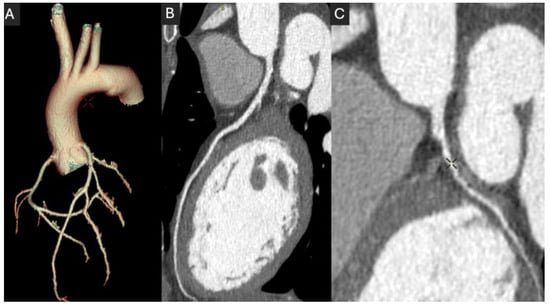

2.2. Coronary Lumen Attenuation